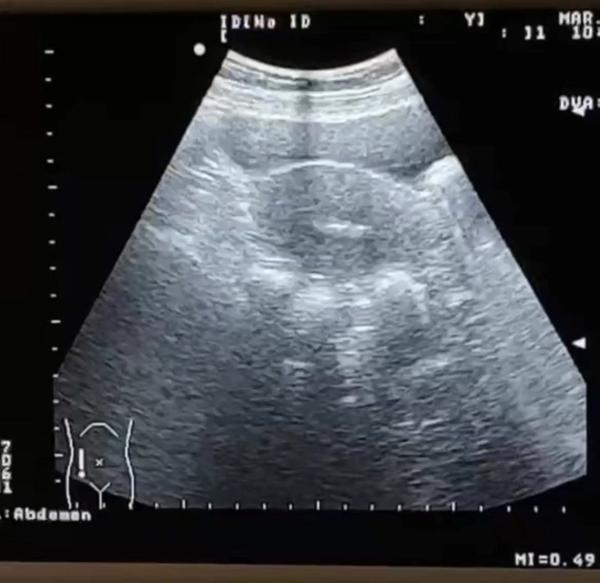

考虑到王女士年龄偏大,胚胎植入前,医护人员做了各项检查,王女士随后接受了一段时间的调养。在身体条件达到最佳状态的时候,生殖医学中心副主任蔡婕主任医师将挑选出来的1枚沉睡了15年的胚胎移植进王女士的子宫内。